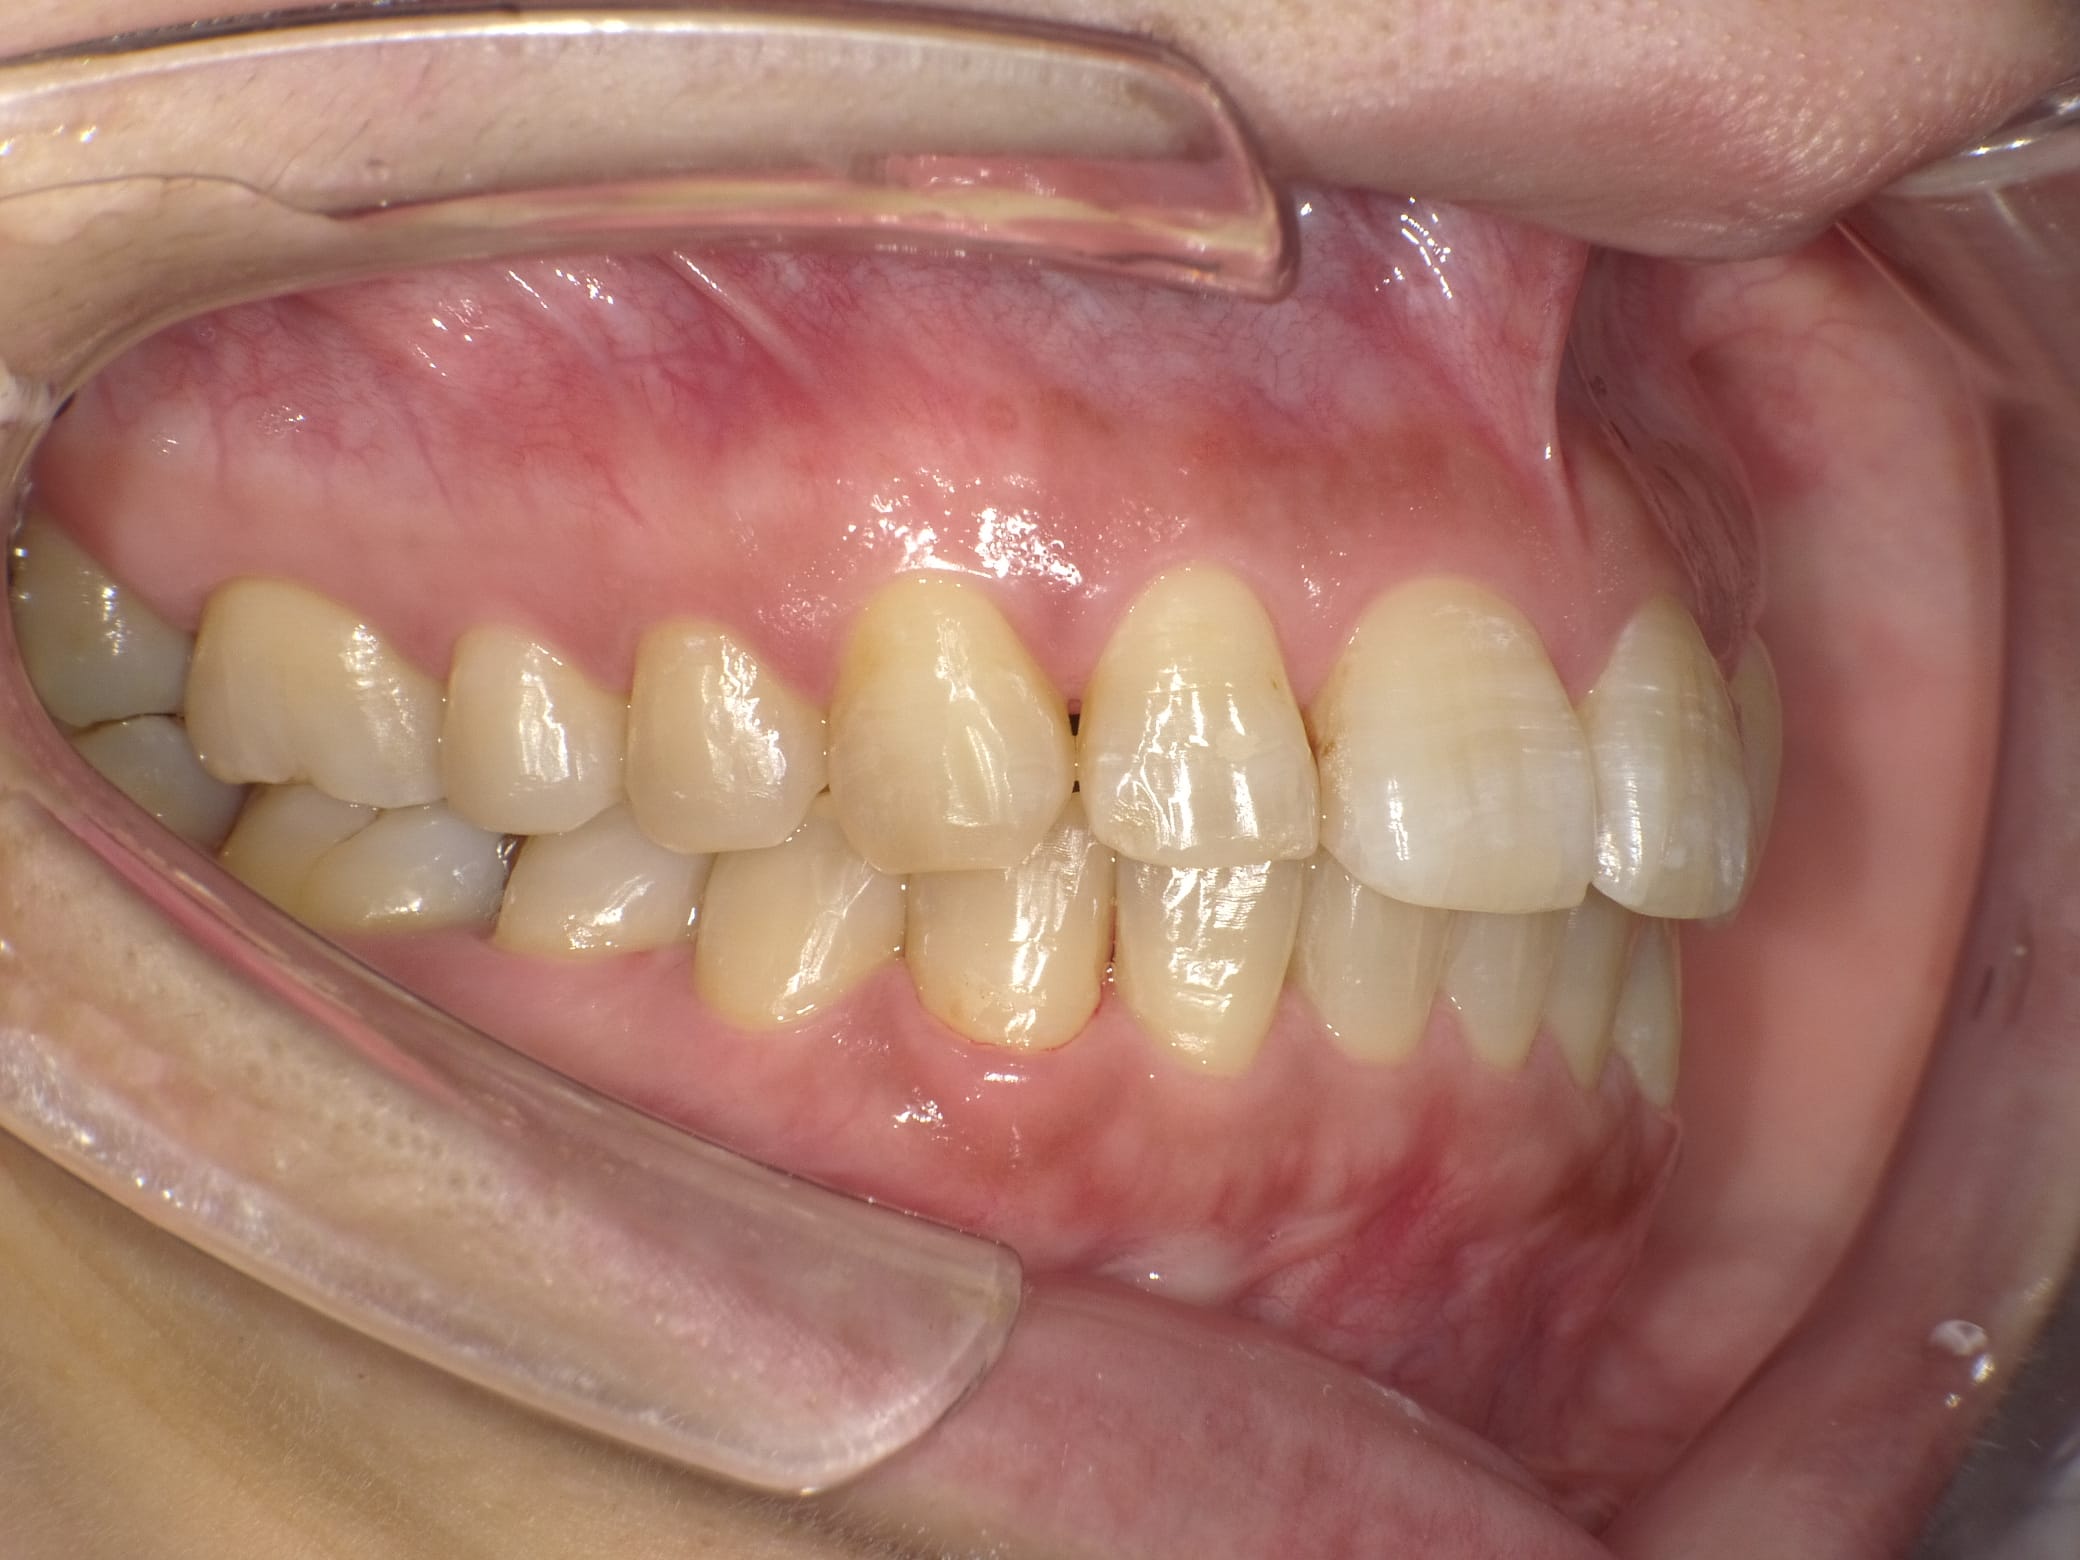

「ずっと放置してしまっていた。今回はちゃんとしっかり治したい」ということで、強い意志をもって来院してくださった患者様の症例です。

インプラント治療、セラミック治療、歯周病治療により、審美性と機能、咬みあわせの再建を行いました。

患者様は咬みあわせの確立により、食事もしやすく、普段の顎関節の状況も良くなり、機能の回復にも満足してくださり、また審美性も喜んでくださいました。

放置期間が長くだいぶ骨が溶けてしまっていたので、前歯部のインプラントは骨の再生療法などが必要だったりしましたが、患者様が治療への前向きな姿勢をだしてくださっていましたので期間も最短で終わりました。

一度放置してしまうと、億劫になってしまってなかなか行動に移すのは難しいと思いますが、少しでも早く治してあげた方が毎日の食事も楽になりますし、お顔の見栄えもお顔の骨格の歪みも改善します。

担当 理事長 佐藤 悠野